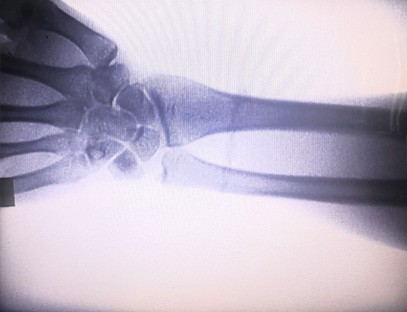

Prenosný röntgenový prístrojje veľmi bezpečný prenosný prístroj s nízkou dávkou žiarenia, ktorý dokáže získať vysokokvalitné snímky pri znížení radiačnej záťaže. Kompenzuje nedostatky veľkých nemocničných zariadení a možno ho kedykoľvek premiestniť a prenášať. Vhodné najmä pre jednotky a jednotlivcov s nedostatočným rozpočtom a nízkymi požiadavkami na obrázky. Náš röntgenový prístroj novej generácie je vybavený 10-palcovou veľkou obrazovkou s vysokým rozlíšením, ktorá má väčší rozsah pozorovacích uhlov a dokáže úplne vidieť cez celú dlaň, vrátane zlomenín, dislokácií, artritídy a kostných nádorov. Dá sa pripojiť k fóliovej tlačiarni na tlač ortopedických fólií a dá sa použiť aj na priemyselnú výrobu a testovanie. Nie je potrebná tmavá komora, priama perspektíva, pozorovanie v reálnom čase. Tento stroj má zobrazovací systém s vysokým rozlíšením, ktorý dokáže veľmi jasne zachytiť snímky akejkoľvek kostnej štruktúry. Poskytovať najlepšie röntgenové testovacie zariadenia a riešenia pre výrobcov medicínskych, domácich zvierat, priemyselných, elektronických produktov, oddelenia kontroly a údržby a výskumné laboratóriá.

špecializácia:Určené pre potreby ortopedických ambulancií, vhodné najmä preröntgenové zobrazovaniekončatín, ako sú ruky, zápästia, lakte, ramená, kolená, členky atď.

Jasné zobrazenie:Na poskytovanie vysokokvalitných röntgenových snímok sa používa pokročilá digitálna zobrazovacia technológia, ktorá pomáha lekárom presne diagnostikovať stav.